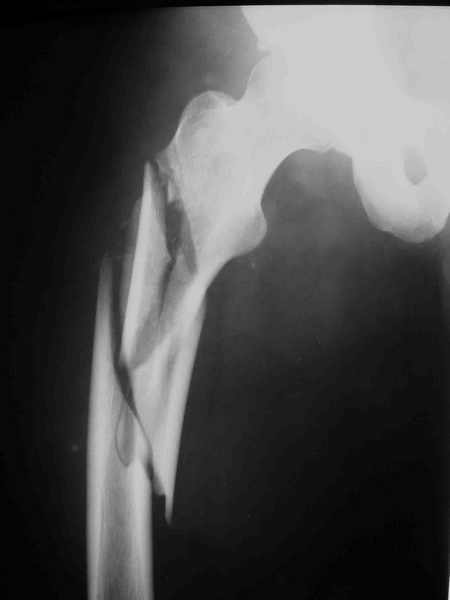

Вот вариант решения похожей ситуации